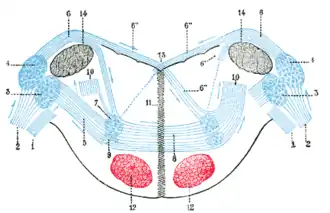

Dorsal cochlear nucleus is #4, at upper left | |

Human caudal brainstem posterior view (Dorsal cochlear nucleus is #5) | |